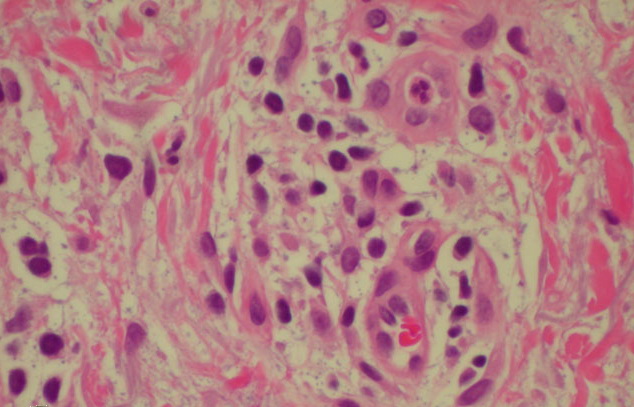

Atlas of skin histopathology